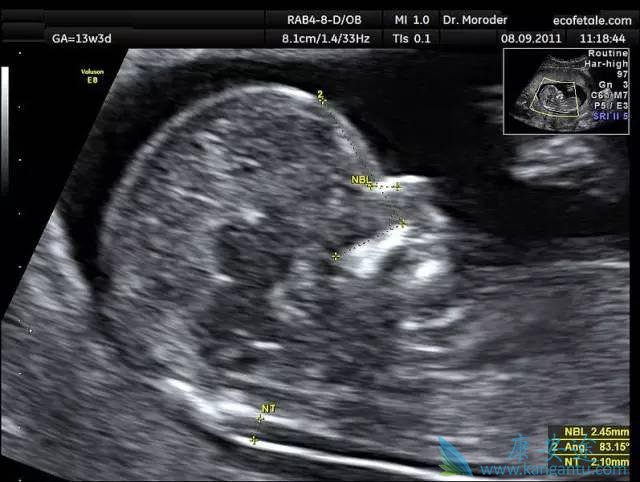

第三次B超检查—孕11-13+6周

这个时期,宝宝已经初见人形,头部、躯干、四肢可以分辨出来了,虽然在超声下可以观察到胎儿活动,但准妈妈通常在这个时期自己无法感知到胎动。此时期超声检查有个很重要的项目——胎儿颈部皮肤透明层厚度(NT),结合早期唐筛结果可以判断胎儿有无染色体异常。这可能妈妈们听得最多的一个检查了吧?有研究数据表明, NT结合唐氏筛查结果,胎儿先天愚型的检出率可达80%。NT检查廉价方便,建议准妈妈们要按时检查。